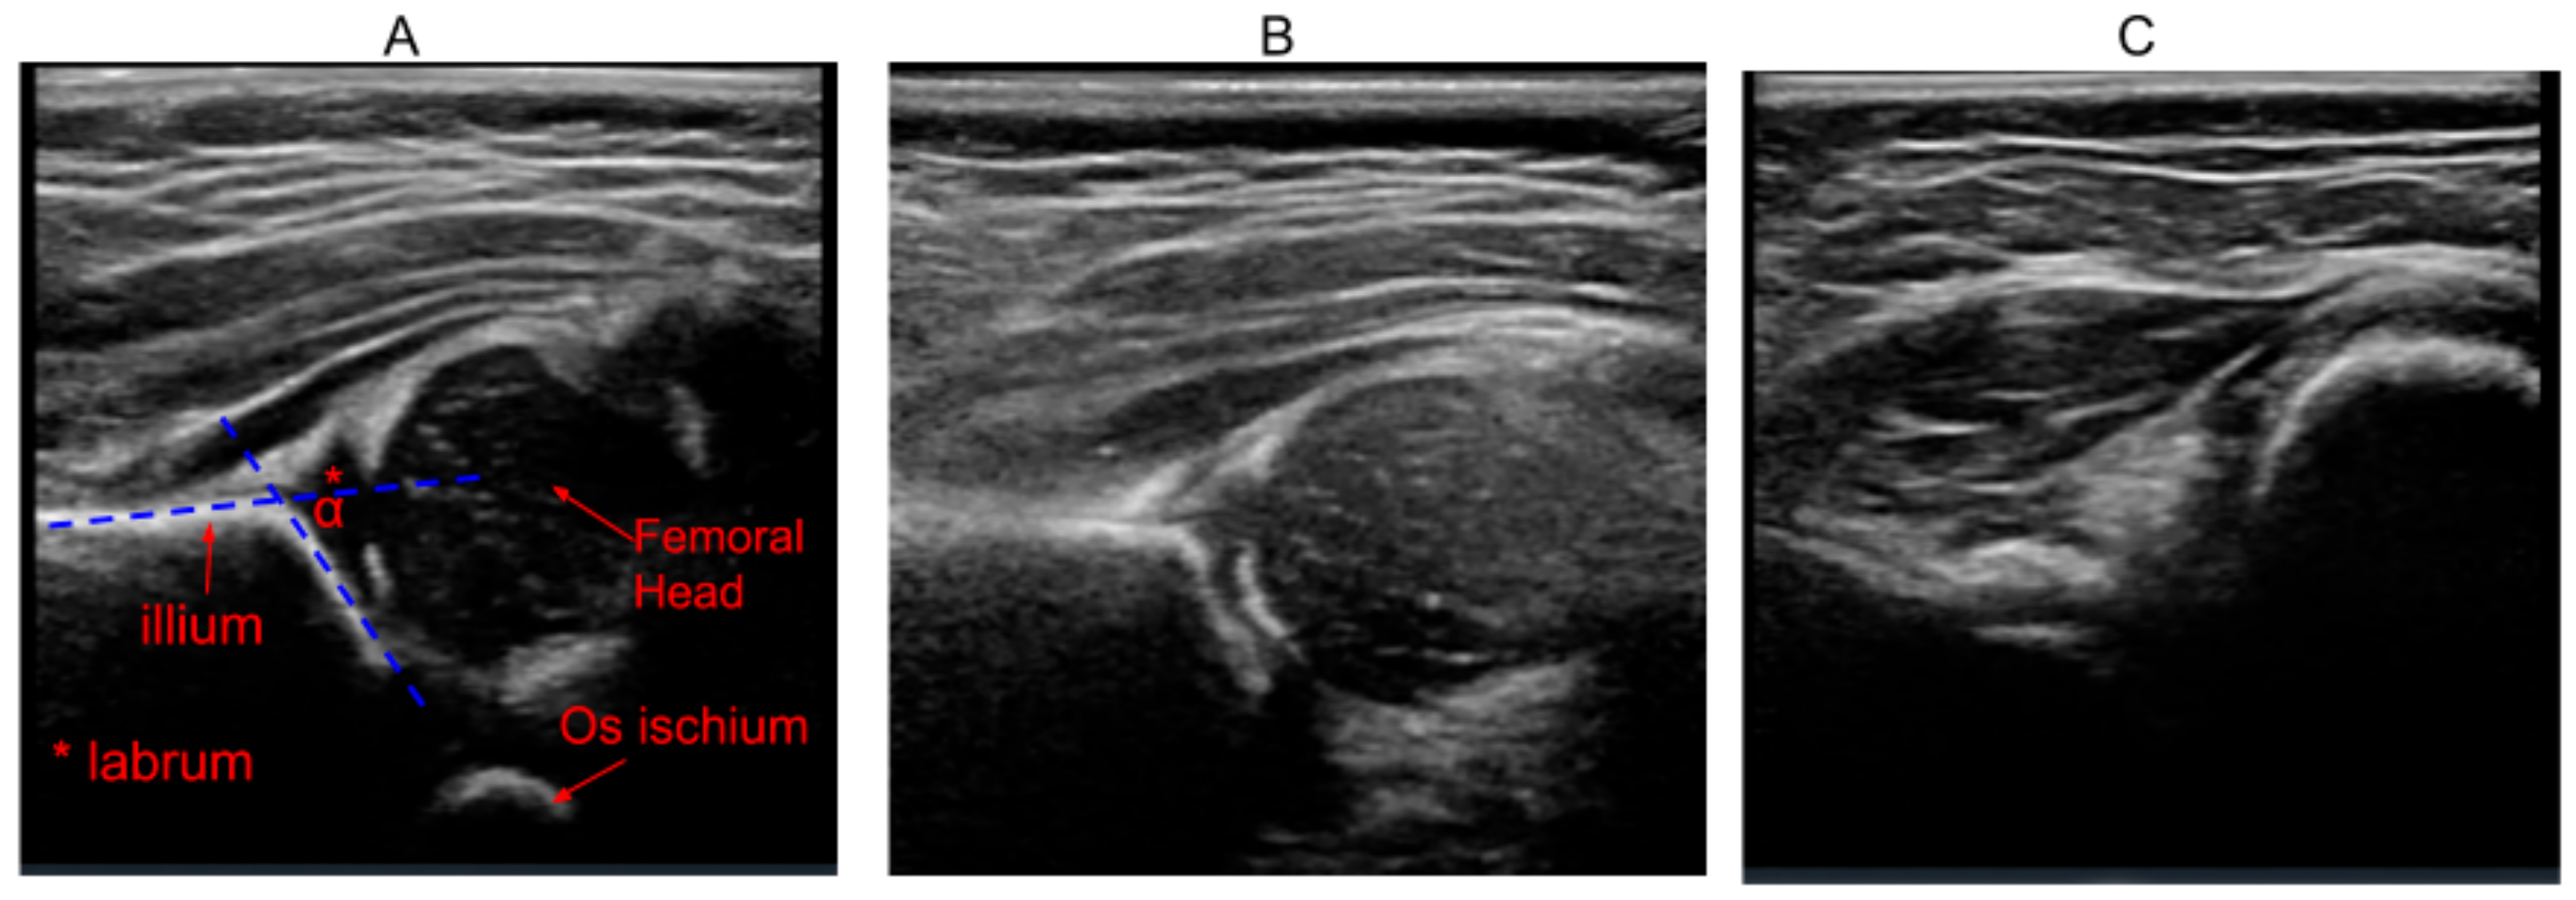

During hip examination, 2D ultrasound images are usually acquired and interpreted based on the Graf technique [14] which measures the alpha angle between the ilium and acetabular roof. Alpha angles greater than 60 degrees are considered normal and those less than 43 degrees are considered severely dysplastic [14]. This technique relies heavily on obtaining a single 2D image in the Graf plane containing all landmarks such as illum, labrum, os ischium and femoral head (Figure 1A). Acquiring such images requires many hours of training, since slight variations in probe orientation can result in suboptimal images. Previous studies have shown that deviation from the Graf plane by novice users can result in incorrect diagnosis in two-thirds of neonates and half of infants evaluated [15]. These variations can be reduced to some extent by using 3D Ultrasound (3DUS). Since 3DUS covers a larger area, it is more likely to contain the Graf plane, thereby making it more reliable than 2DUS, especially when scanning is performed by novice sonographers [16].

Figure 1. Examples of ultrasound hip images of different scan quality. (A) Example of a high-quality image in which all landmarks such as ilium, os ischium, labrum and femoral head are clearly visible. The alpha angle is measured as the inner angle between the iliac line and acetabular roof. (B) Moderate-quality scan containing all landmarks, but with the blurring of the os ischium and blurring and slight tilt of the iliac line. (C) Poor-quality image with none of the landmarks visible.

However, in both 2DUS and 3DUS, reliability of the ultrasound examination depends to a large extent on scan quality. In current clinical practice, sonographers manually assess scan quality based on visibility of key landmarks. This approach is prone to high inter-observer variance. As a result, poor-quality images can be presented to radiologists, risking misdiagnosis. Examples of images of varying scan quality are shown in Figure 1. In earlier work [17], a semi-quantitative scoring technique that evaluates individual imaging landmarks (such as ilium, labrum, femoral head and os ischium) and artifacts (such as movement and other artifacts) is proposed. While such approaches make scan quality assessment less subjective, there can still be variability in the manual assessment of individual features.